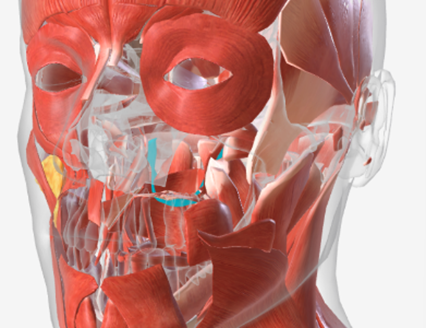

Superior pharyngeal constrictor

origin is on the pterygomandibular raphe, coursing posteriorly to insert on the median raphe of the pharyngeal aponeurosis function is to pull the pharyngeal wall forward to constrict the pharyngeal diameter

Superior Pharyngeal Constrictor

|  |  |

Superior pharyngeal constrictor

A

Superior pharyngeal constrictor

F

Superior pharyngeal constrictor

A

Superior pharyngeal constrictor

E

Superior pharyngeal constrictor

E